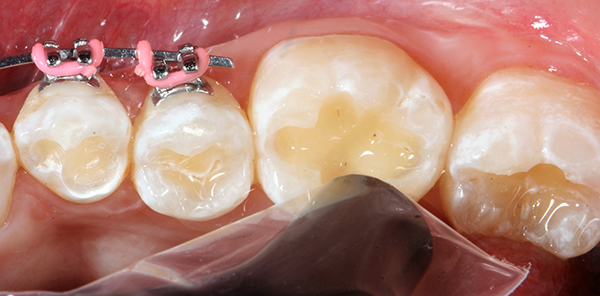

Using the Ball-Point Applicators, I applied a generous amount of OptiBond All-In-One adhesive to the enamel/dentin surface. I scrubbed the surface with a brushing motion for 20 seconds, and then applied a second application of OptiBond All-In-One adhesive with a brushing motion for 20 seconds. I then dried the adhesive with gentle air first and then medium air for five seconds with oil-free air, and then light cured for 10 seconds with the Kerr Demi™ Plus Curing Light (Fig. 3).

Fig. 3 Fig. 4

I then filled the preparation with bulk fill composite (Fig. 4). The composite of choice for this case was SonicFill™3 (Kerr), which is a sonic-activated bulk fill composite.